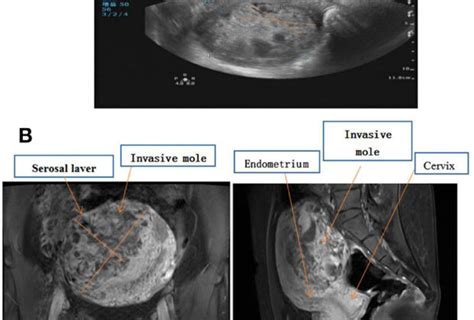

The diagnosis of hypertrophic elongation of the cervix is typically made through a combination of methods. A pelvic exam is usually the first step. Your doctor can feel the cervix and get a general sense of its size and consistency. However, to accurately measure its length and assess its structure, imaging techniques are crucial. Ultrasound , particularly transvaginal ultrasound, is the gold standard. This involves inserting a small probe into the vagina, which provides a clear, detailed image of the cervix, allowing for precise measurement of its length and assessment of its internal structure. In some instances, an MRI might be used for a more detailed view, especially if other anatomical structures need to be evaluated.